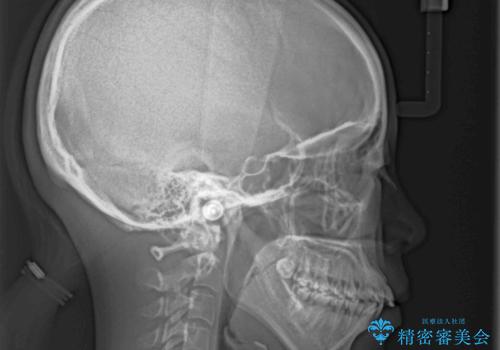

- 口元の突出感と上下前歯のでこぼこを気にして来院された患者様です。

上下前歯部叢生のスペース獲得のため、上下顎左右小臼歯各1歯(計4本)を抜歯して、矯正治療を行うこととしました。